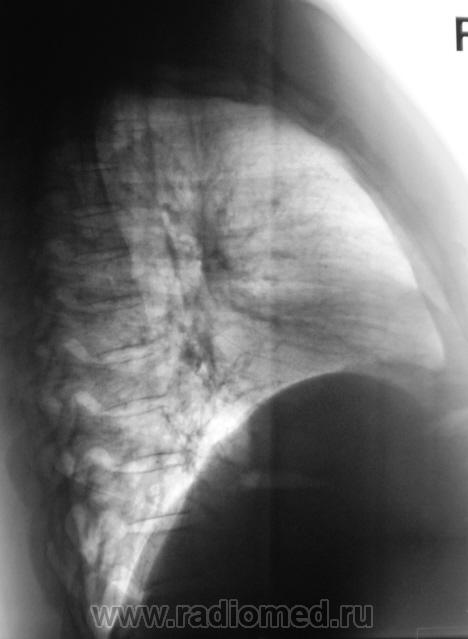

Пациент, после анализа флюорограмм "взят на контроль". Произведено стандартное дообследование - рентгенография в прямой и правой боковой проекциях, боковая томография. По большому счету, пациет жалоб не предъявляет.

Вначале думал о центральном раке, ателектазе, но на томограммах видно четко бронхи "воздушная бронхограмма". Может пневмония?.

Массивное затемнение "вне анатомических границ", рождает сомнения по поводу "осумкования". Что за снижение прозрачности "сзади", но фоне чего хорошо дифференцируется бронх - думаю, что "инфильтрация". пациент в стационаре, назначена противовоспалительная терапия. По всей видимости, динамика будет выставлена, если "область не заберет на себя".

Мыслей о междолевом осумкованном плеврите нет, т.к. контуры не ровные, о центральном раке не думаю т.к. бронхи говорят об их интактности, думаю пока о пневмонии. Динамика в данном случае, в паре с лечением должа дать ответ.